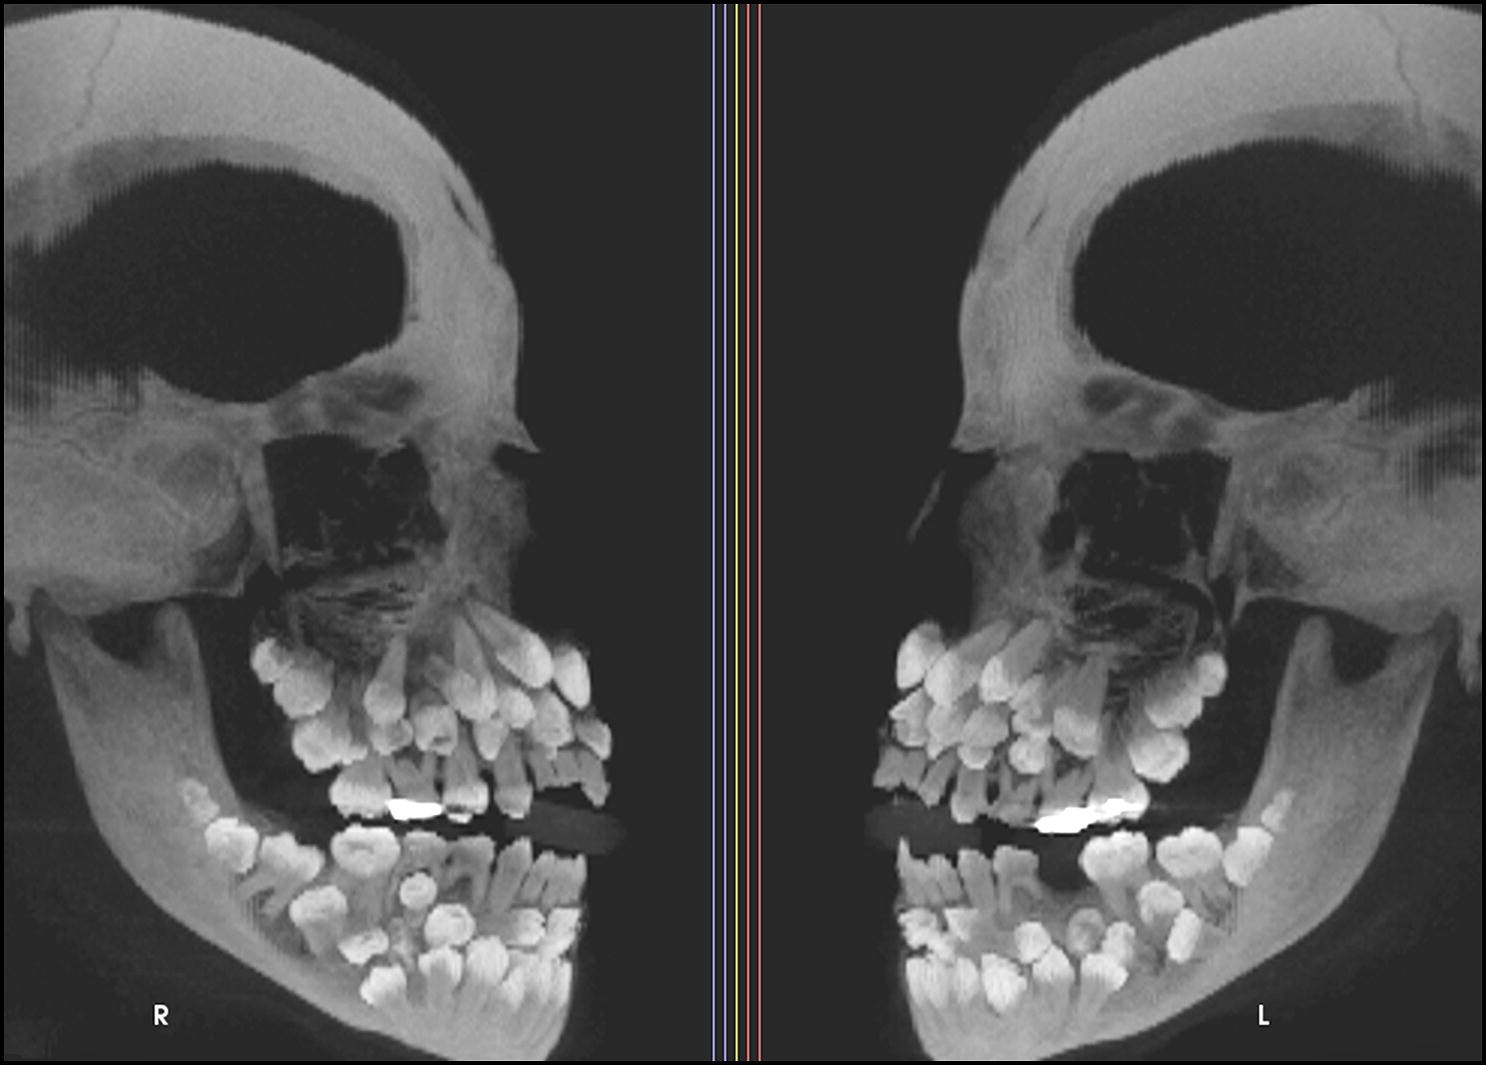

Monsieur-Hulot a écrit : ↑jeu. 25 sept. 2025 14:27Hyperdontie ! J'attends l'hypercouillie avec une impatience non dissimulée !

On dirait quelqu'un qui a avalé une poignée de pop corn

Y'en a un peu de trop et des fois se sont les ustensiles qui sont mal rangés !Unserious Sam a écrit : ↑jeu. 25 sept. 2025 16:48On dirait quelqu'un qui a avalé une poignée de pop corn